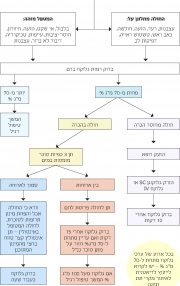

| 13:54, 14 ביוני 2017 | טיפול בהיפוגלקמיה.png (קובץ) |  |

344 קילו־בייטים | Motyk | 1 | |